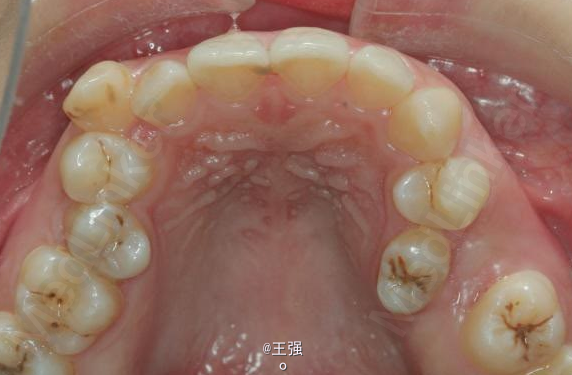

又一例不对称拔牙

牙弓狭窄,牙列拥挤

不对称拔牙